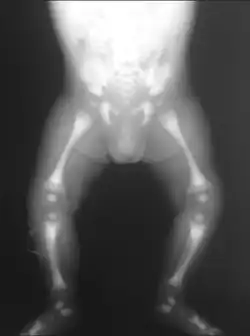

Autosomal recessive osteopetrosis (ARO), also known as malignant infantile osteopetrosis or infantile malignant osteopetrosis (IMO), is a rare type of skeletal dysplasia characterized by a distinct radiographic pattern of overall increased density of the bones with fundamental involvement of the medullary portion. Infantile osteopetrosis typically manifests in infancy. Diagnosis is principally based on clinical and radiographic evaluation, confirmed by gene analysis where applicable.[5] As a result of medullary canal obliteration and bony expansion, grave pancytopenia, cranial nerve compression, and pathologic fractures may ensue. The prognosis is poor if untreated. The classic radiographic features include endobone or "bone-within-bone" appearance in the spine, pelvis and proximal femora, upper limbs, and short tubular bones of the hand. Additionally, there is the Erlenmeyer flask deformity type 2 which is characterized by the absence of normal diaphysial metaphysical modeling of the distal femora with abnormal radiographic appearance of trabecular bone and alternating radiolucent metaphyseal bands.[5]